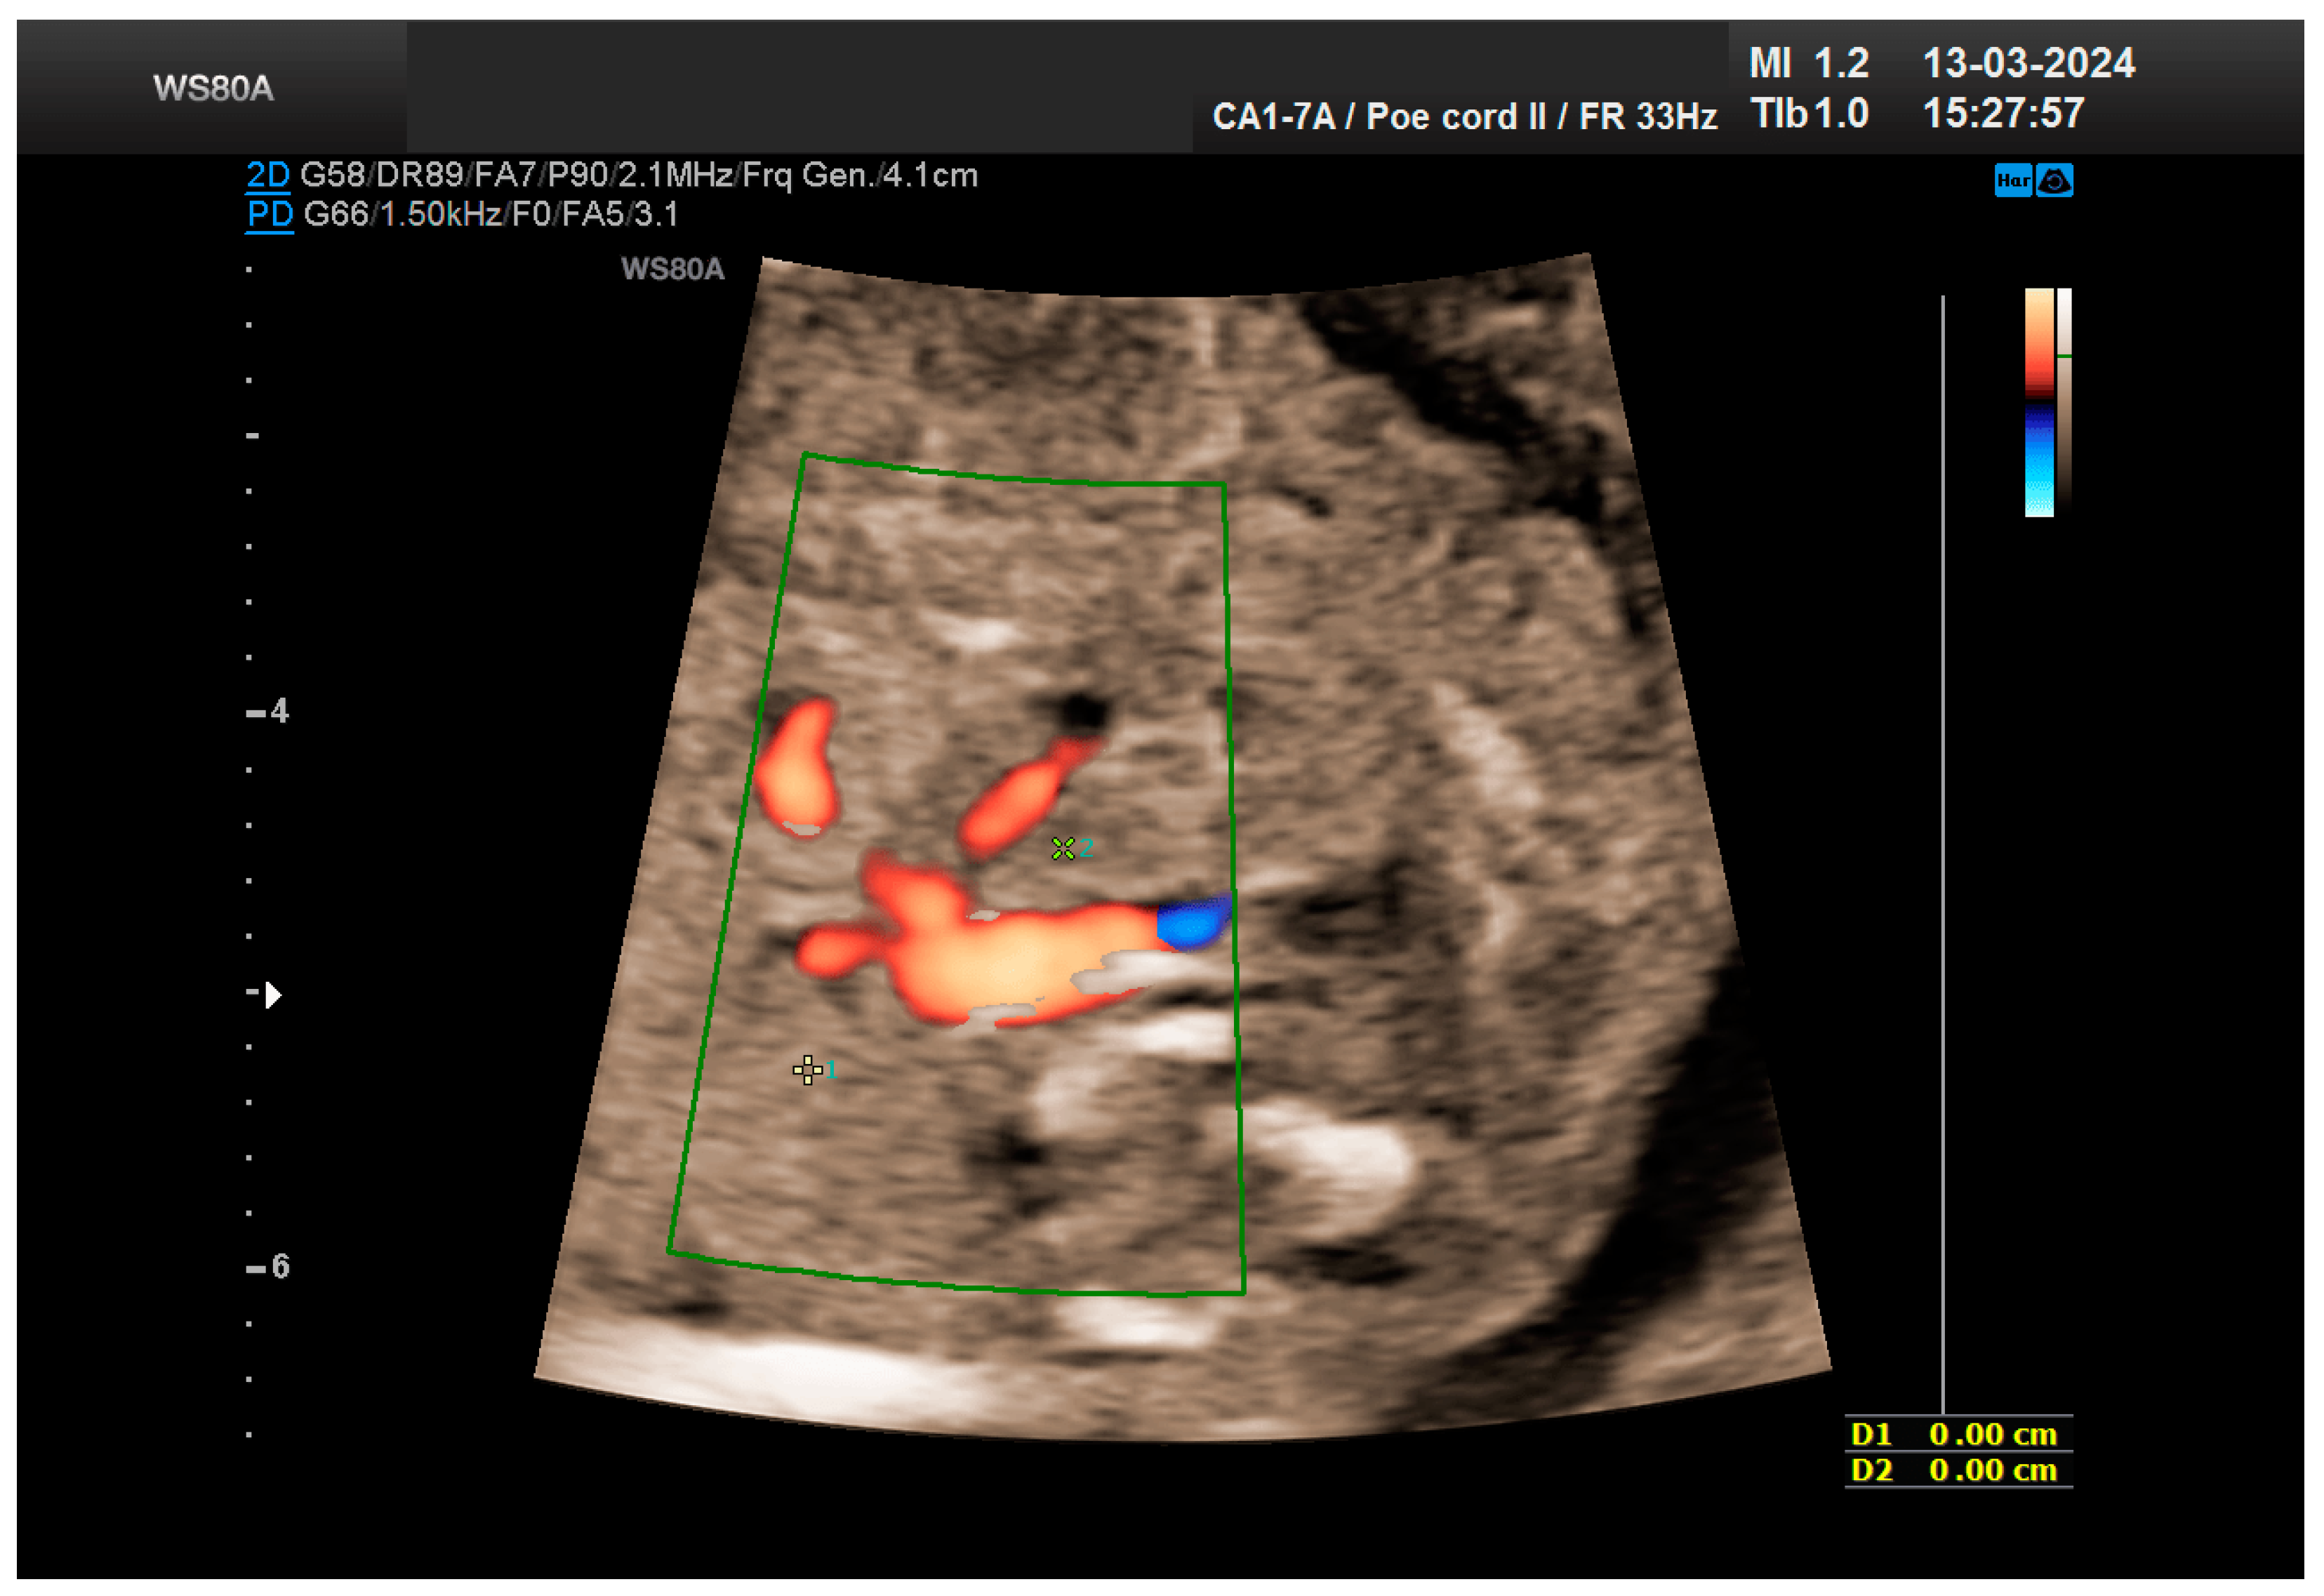

The combined test result indicated a low risk for trisomies, preeclampsia, and intrauterine growth restriction. However, during the ultrasound examination, the absence of the right renal tissue in the right parasagittal sections was noted (Figure 1). Examination of the embryo in axial sections demonstrated the presence of a relatively well-defined acoustically heterogeneous echogenic mass situated anterior to the spine, in sonographic contact with the renal tissue image correctly occupying the left lumbar fossa (Figure 2). Those aspects suggested the existence of a renal anomaly of crossed fused renal ectopia. No other embryonic anomalies were detected, the bladder image was present, and the amniotic fluid volume was normal. The calculated gestational age corresponded to the ultrasound estimate. The suspicion of crossed fused renal ectopia was maintained during a subsequent reevaluation at 17 weeks of pregnancy (Figure 3 and Figure 4).

The patient returned at a gestational age of 22 weeks for a second-trimester ultrasound screening. During this examination, the suspicion of crossed fused renal ectopia was confirmed. Axial sections revealed a normal kidney image in the left lumbar fossa and another one, anterior to the spine, without reaching the right renal fossa, fused with the normal left kidney (Figure 5). Two sources of arterial vascularization could be identified, both of them with origins in aorta as follows: one correctly originating from the lumbar aorta, serving the normally positioned left kidney, and another appearing to originate on the anterior border of aorta, at the same level, supplying the ectopic right renal tissue mass (Figure 4 and Figure 6). The bladder was present, with normal appearance and volume. No left ureterohydronephrosis was detected. The presence and course of the right ureter could not be identified. The amniotic fluid volume was normal. No other severe or minor anomalies were observed.

Figure 4. The vascularization of the “renal mass” seems to originate in the aorta. Green box—color Doppler window.

Figure 6. The two kidneys fused with aortic arterial vascularization. Green box—color Doppler window.